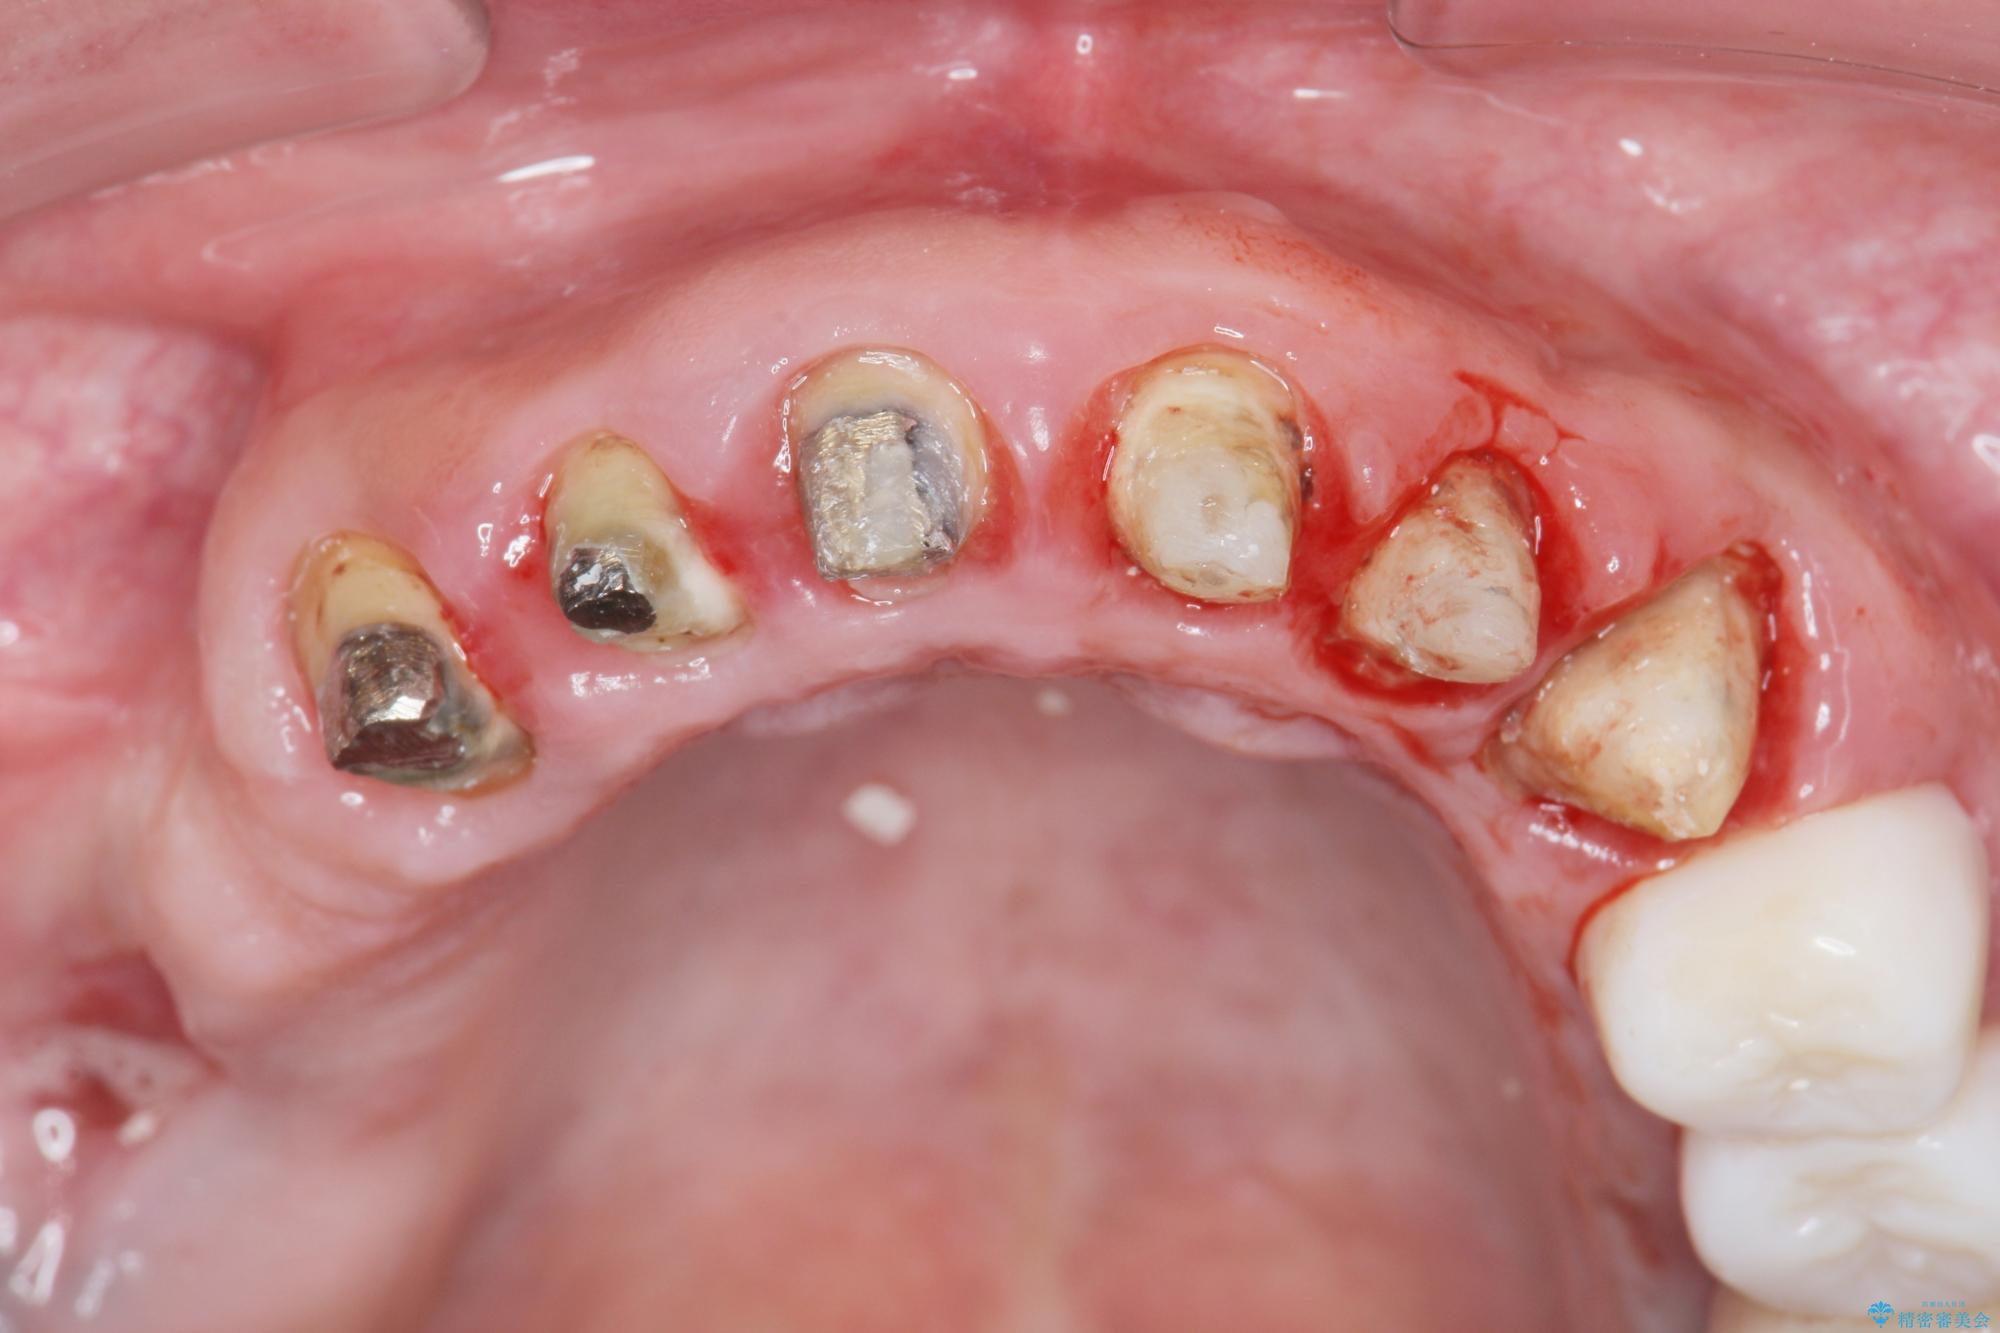

歯周組織検査を行うと歯ぐきからは容易に出血し、X線検査より歯とセラミッククラウンの適合が悪い(ピッタリと合っていない)状態が示唆され、歯ぐきの炎症を惹起している状態でした。

セラミッククラウンを除去し仮歯を装着し、歯周外科手術を行い歯ぐきの状態を改善したのち、適合の良いセラミッククラウンを再作製をする治療計画としました。